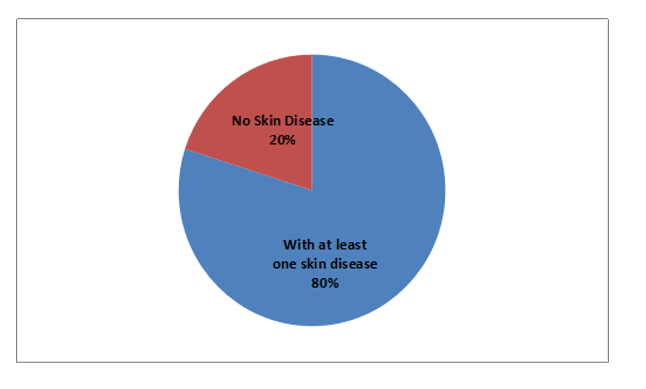

Climate change impacts are observed by the farmers in both study sites and they have attempted to address the impacts through adaptation choices. The study sites in Madi valley has mixed ethnicity, whereas Deukhuri has more than 95% Tharus. Maximum respondents were married and dependent on agriculture for their livelihood in both sites. Linear probability model was used to analyze the binary or dichotomous outcome variable with number of explanatory variables. Crop diversity, education, training and total land holding (acre) were positively significant for adaptation choices in the studied households in the study sites. Rest of the variables were not significant though indicated positive as expected except age, occupation, ethnicity, family size, and access to credit. No any noteworthy difference in understanding climate change and adaptation choices in these sites at the household level. It is recommended to maintain and enhance the crop diversity in the total land holding through crop diversification, mixed farming, agro-forestry and integration of fruits, perennial crops in the same unit of land. The education and training on agricultural practices and climate adaptation are influential in adaptation choices, thus the government and other stakeholders should focus on additional training and educational activities to strengthen the climate adaptation.